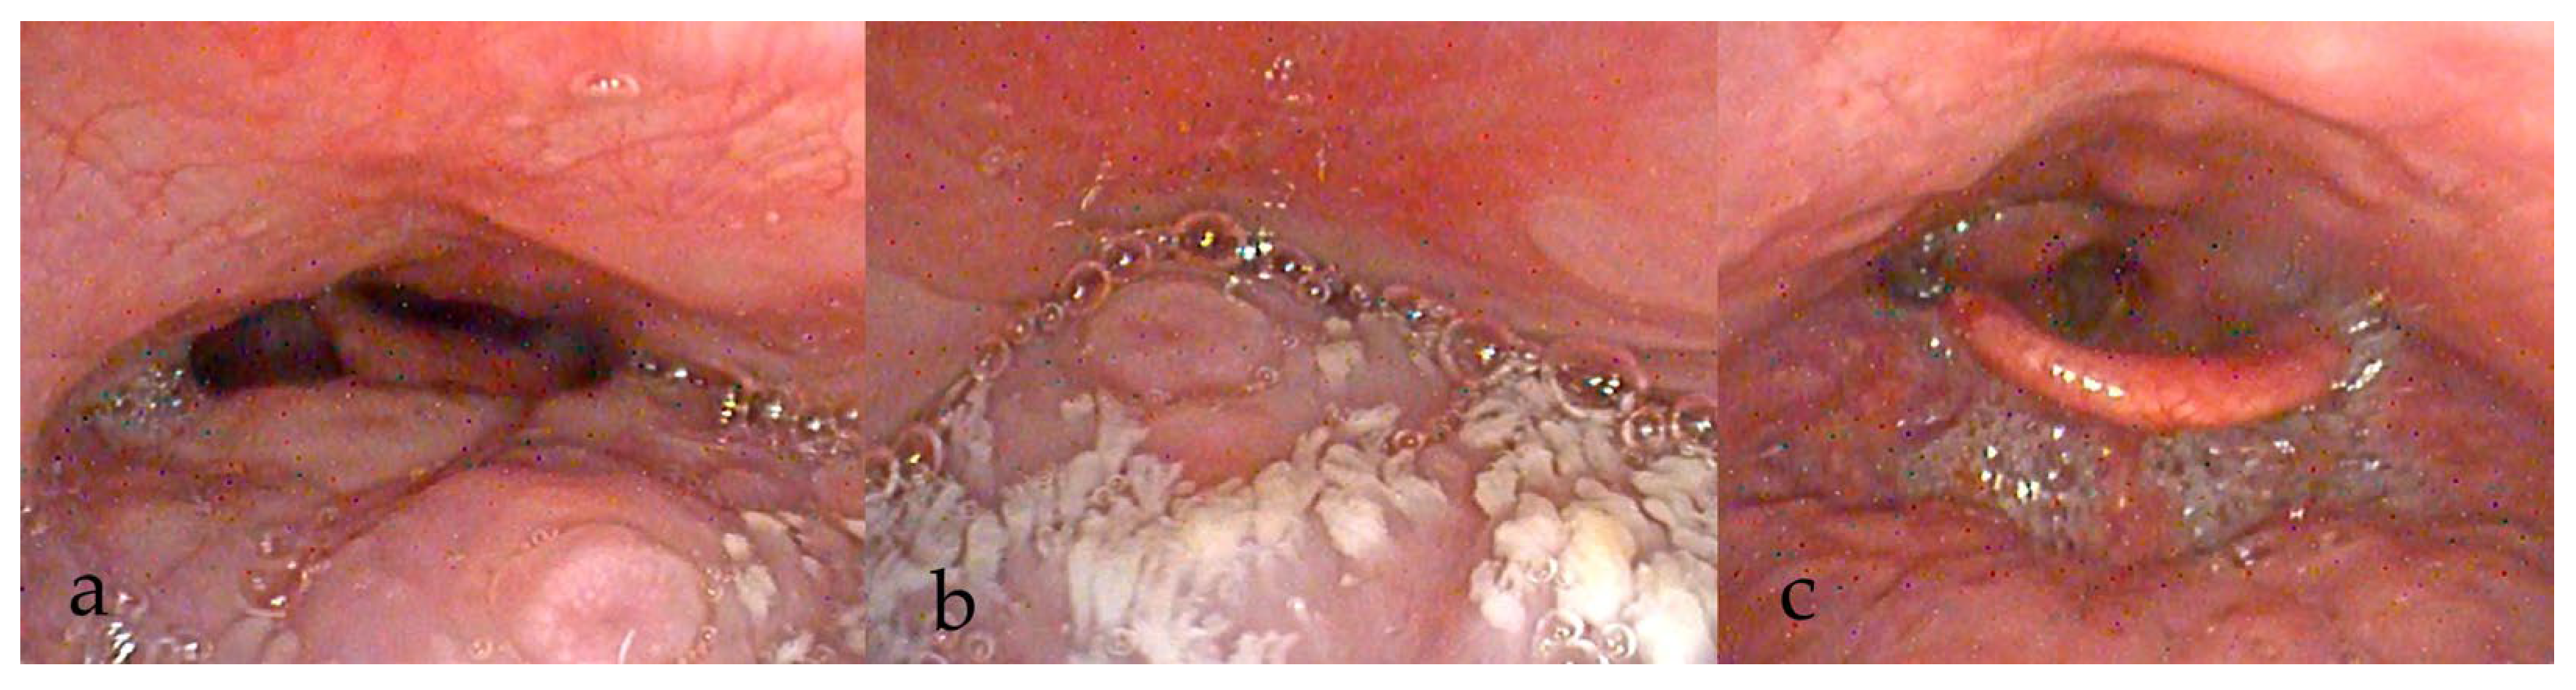

3.3. During DISE (Figure 1)

3.3.8. Documentation